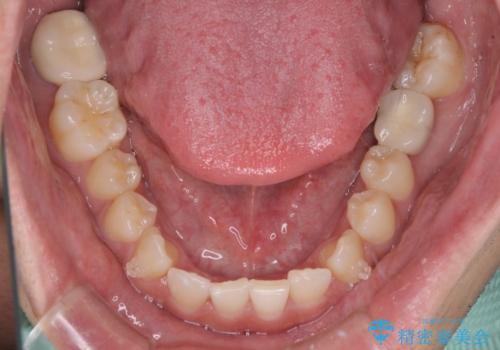

- 上顎前歯の隙間を気にして来院された患者様です。

下顎前歯に叢生がありましたが、特に気にしていらっしゃいませんでした。

下顎臼歯にインプラント補綴治療がされており、全顎治療するにはクラウンの作り替えが必要となる旨を説明し、ワイヤー装置により上顎のみの矯正治療を行うこととしました。

下顎前歯の叢生解消も提案しましたが、上顎の隙間が閉じたことで満足されました。